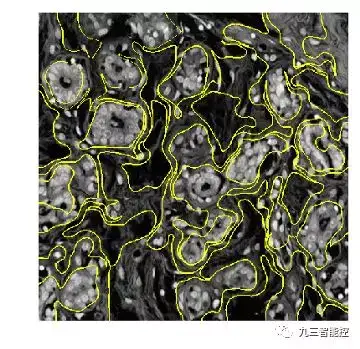

超像素(Super Pixel)

超像素(SuperPixel),就是把原本多个像素点,组合成一个大的像素。超像素由一系列位置相邻且颜色、亮度、纹理等特征相似的像素点组成的小区域。这些小区域大多保留了进一步进行图像分割的有效信息,且一般不会破坏图像中物体的边界信息。